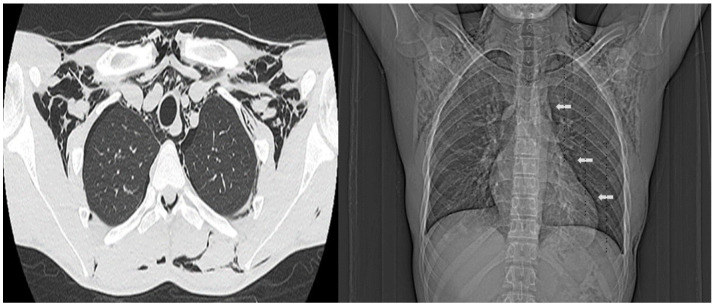

1939 年,哈曼氏综合征(Hamman´s Syndrome)又称自发性气胸,其特征是出现气胸、皮下气肿和气臌。据认为,它是由阴道分娩时的气压创伤引起的,导致肺泡膜破裂和随后的漏气。临床表现通常没有特异性。根据症状严重程度和并发症的不同,治疗策略也有所不同,高浓度氧疗可促进空气吸收。我们介绍了一名 18 岁男性患者的病例,该患者有支气管哮喘和吸烟史,强调了在类似病例中提高对哈曼综合征认识的必要性。及时诊断和适当治疗对于预防或快速处理潜在的危及生命的并发症至关重要。在男性患者中诊断这种综合征尤其具有挑战性,因为它最初与阴道分娩的并发症有关,可能导致较差的预后。

In 1939, Hamman´s syndrome, also know as spontaneous pneumomediastinum, was characterized by the presence of pneumothorax, subcutaneous emphysema, and pneumorrhachis. It is believed to arise from barotrauma during vaginal labor, causing alveolar membrane rupture and subsequent air leakage. Clinical manifestations are often nonspecific. Management strategies vary based on symptom severity and complications, high-concentrations oxygen therapy promoting air absorption. We present the case of an 18-year-old male patient with a history of bronchial asthma and tobacco use, underscoring the need for heightened awareness of Hamman´s syndrome in similar cases. Prompt diagnosis and appropriate management are crucial to prevent or quickly address potential life-threatening complications. Diagnosing this syndrome in male patients can be particularly challenging, as it was initially associated with complications from vaginal labor, potentially leading to poorer outcomes.